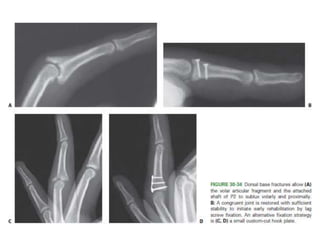

Axial loading patterns ,

• Partial articular fractures

– Dorsal base

Middle Phalanx Fracture- Treatment Options

• Condylar fractures

– CRIF- converging or diverging.

Middle Phalanx Fracture-Treatment Options • Static Splinting. – Crushing- comminution with no significant displacement. • Dynamic Extension Block Splinting. – Volar base of P2 - less than 40% of the articular surface • Condylar fractures – CRIF- converging or diverging. • Unstable shaft fractures – CRIF – K wiring – ORIF – Lag screw fixation – if rotational instabiity. – Plate and screw fixation – if axial instability.